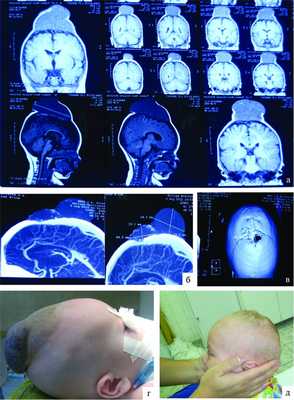

Рисунок 1. Наблюдение 1 (больной М.). а - спиральная КТ-ангиография; б - спиральная КТ с 3D костной реконструкцией; в - селективная церебральная ангиография; г - интраоперационные фотографии (этапы операции); д, е - внешний вид больного до и после операции. При проведении спиральной компьютерной томографии (СКТ) с ангиографией с 3D-реконструкцией костей свода и основания черепа определяются гипертрофированные с наличием крупных лакун вены затылочной области справа, которые через дефект в лямбдовидном шве размером 12×9,4 мм дренируются в правую половину поперечного синуса через атипичную эмиссарную вену (см. рис. 1, б). При селективной церебральной ангиографии в артериальную фазу (см. рис. 1, в) данных о наличии артериовенозной мальформации головного мозга не выявлено. Определяется атипичная вена, отходящая от правой половины поперечного синуса, дренирующаяся в экстракраниальную венозную лакуну в правой затылочной области. Больному было проведено оперативное вмешательство, которое заключалось в разобщении правой половины поперечного синуса и экстракраниальных варикозно-расширенных вен и венозных лакун. Интраоперационно отмечалось их спадание (см. рис. 1, г). Трофических изменений кожного лоскута не выявлялось. Больной был выписан под наблюдение невролога (см. рис. 1, е).

Рисунок 2. Наблюдение 2 (больной Д.). а - спиральная КТ-ангиография; б - спиральная КТ с 3D костной реконструкцией; в - МРТ; г, д - внешний вид больного до и после операции.

При МРТ головного мозга в мягких тканях головы (см. рис. 2, а) выявляется образование, состоящее из двух частей - 30×48 и 40×17 мм. На спиральных компьютерных ангиограммах (см. рис. 2, б) определяется экстракраниальное образование в задних отделах лобной области и медиальных отделах обеих теменных областей, состоящее из двух частей размером 30×48 и 40×17 мм, вызывающих атрофию от давления обеих теменных костей (костный дефект чешуи лобной кости (см. рис. 2, в) в области большого родничка размером 128×25 мм), дренирующееся из передней камеры в среднюю треть верхнего сагиттального синуса; приводящих артериальных сосудов не выявлено. Больному было проведено двухэтапное микрохирургическое вмешательство. В послеоперационном периоде признаков венозной гипертензии не отмечалось, очаговая симптоматика не выявлена, косметический дефект отсутствует (см. рис. 2, д).